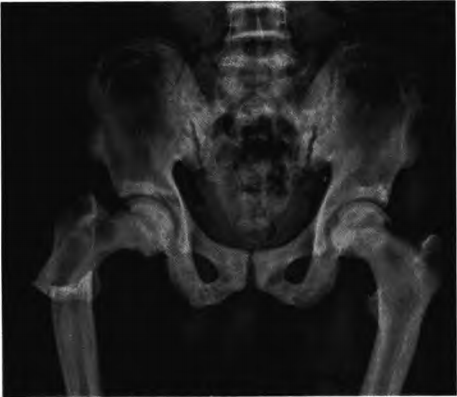

图2.术前骨盆正位X线片示右股骨粗隆下骨折,断端移位明显,髂骨翼呈“同心圆征”

X线检查:①全身多发骨密度增高,骨小梁粗糙、模糊,骨皮质厚,髓腔窄小;②椎体呈“夹心蛋糕样”特征性改变;③两侧髂骨翼呈典型“同心环状征”;④双侧髋关节、膝关节软骨下骨密度增高,关节间隙窄(见图1~2)。